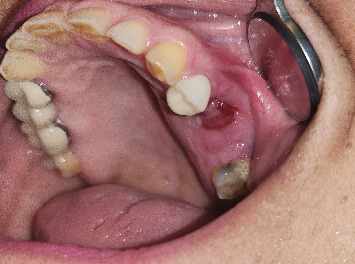

Medication-related osteonecrosis of the jaw (MRONJ) is a well-known side effect of bone-modifying agents such as antiresorptive medications including pamidronic and zoledronic acids (intravenous bisphosphonates) and denosumab (anti-RANK ligand humanized monoclonal antibody). The major risk factor for the precipitation of MRONJ in a patient taking antiresorptive medication is dentoalveolar trauma such as dental extractions. Management of MRONJ in oncology patients is exceptionally challenging. In this report, two multiple myeloma patients with longstanding advanced-stage MRONJ were successfully managed with combined pentoxifylline-tocopherol treatment pre- and postextraction/sequestrectomy. In conclusion, based on this report and other published reports, it appears that the use of combined pentoxifylline-tocopherol protocol in the management of MRONJ is effective.